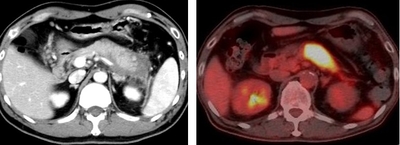

仮説を検証するため、まず、3種類のAhR活性化分子の投与が、実験的自己免疫性膵炎の発症に及ぼす効果を検討しました。自己免疫疾患モデル動物であるMRL/MpJマウスに、Poly(I:C)(合成二本鎖RNA:ウイルス由来の二本鎖RNAと同等の免疫賦活作用を有する)を繰り返し投与することにより、自己免疫性膵炎を誘導しました。この自己免疫性膵炎モデルマウスに対して、ダイオキシンの一種である2, 3, 7, 8-テトラクロロジベンゾジオキシン、ブロッコリーに多く含まれるインドール系化合物の一つであるIPA(インドール-3-ピルビン酸)、植物由来生薬である青黛の3種類のAhR活性化分子を含む餌を与えました。その結果、3種類全てのAhR活性化分子の投与が、効率良く自己免疫性膵炎の発症を防ぐことを見出しました。

次に、AhR活性化による自己免疫性膵炎の制御メカニズムを検証した結果、AhRの活性化に伴い、膵臓にIL-22が多く産生されていることを発見しました。また、IL-22を中和する抗体を投与すると、AhR活性化分子を投与しても膵炎の発症は抑制されませんでした。さらに、AhR活性化によりIL-22を産生するのは、膵ランゲルハンス島※7 のα細胞であることを突き止めました。

IL-22は組織修復機能を持ち、炎症を制御することが知られており、AhR活性化分子の投与により膵ランゲルハンス島で産生されたIL-22も、同様の効果が期待できます。検証の結果、膵ランゲルハンス島で産生されたIL-22は、自己免疫性膵炎の特徴である腺房-導管異形成※8 の発生を抑制し、膵臓腺房構造の恒常性の維持に寄与することが示唆されました。

また、自己免疫性膵炎患者でも、ステロイド治療により病気の状態が改善すると、血清中のIL-22が大きく増加することも明らかになり、AhR活性化によるIL-22の増加が、自己免疫膵炎の発症抑制に寄与していることが明らかになりました。

本研究により、自己免疫性膵炎の発症メカニズムの解明や新規治療法の開発への新たな一歩に繋がることが期待されます。現在、近畿大学病院において、自己免疫性膵炎患者を対象として、青黛(試験薬名:青黛腸溶FC錠)を用いた臨床研究(試験ID:jRCTs051210171)を実施しており、青黛の安全性・有効性を確認する予定です。